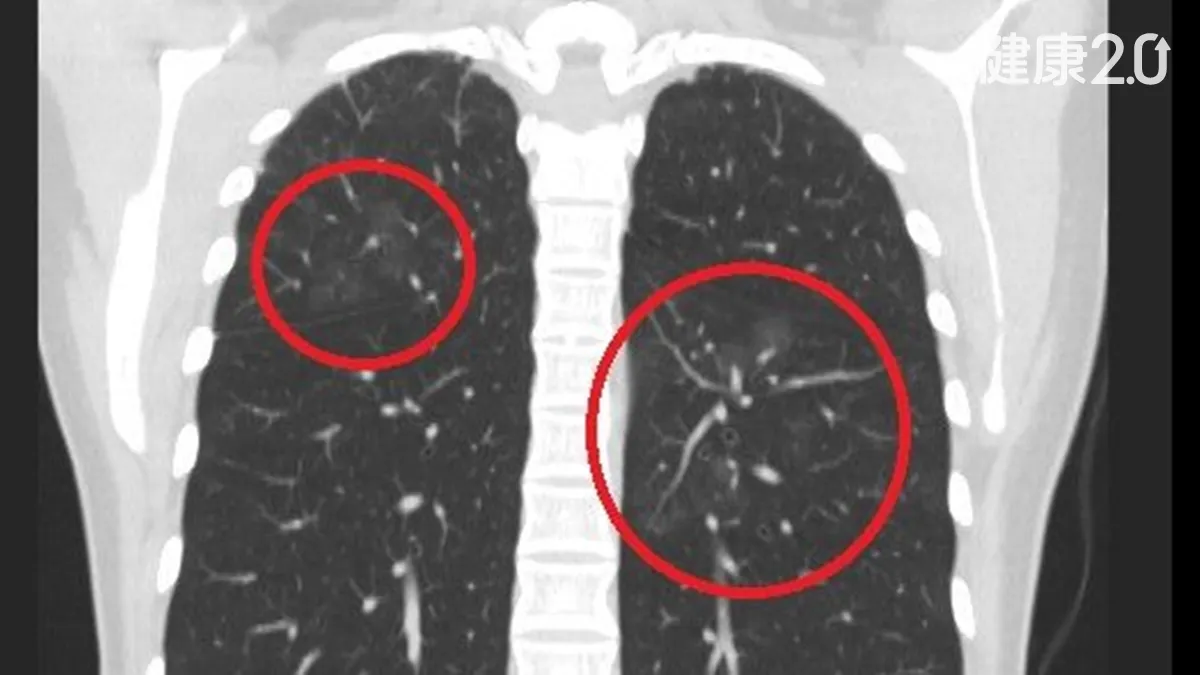

健檢發現肺結節快手術?醫建議多評估 有機會用「這種藥」就能清除免挨刀!

肺癌名列113年國人10大癌症死亡人數第一名,而且有逐年增加的趨勢,不少有肺結節的民眾為預防變成肺癌,急著開刀切除,不過